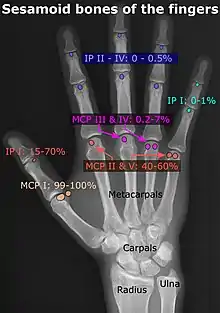

- Location and structure: Erica Chu, Donald Resnick. "MRI Web Clinic — June 2014: Sesamoid Bones: Normal and Abnormal". Retrieved 2017-11-04.

- Prevalences: Chen W; Cheng J; Sun R; Zhang Z; Zhu Y; Ipaktchi K; et al. (2015). "Prevalence and variation of sesamoid bones in the hand: a multi-center radiographic study". Int J Clin Exp Med. 8 (7): 11721–6. PMC 4565393. PMID 26380010. - "Poster Abstracts" (PDF). Association for Sports Medicine of Serbia (Udruženje za medicinu sporta Srbije). 2006. Retrieved 2017-11-03., citing: Natsis K.; Beletsiotis A.; Terzidis I.; Gigis P. "A study of the accessory bones of the foot. Incidence in the Greek population-clinical significance" (PDF).